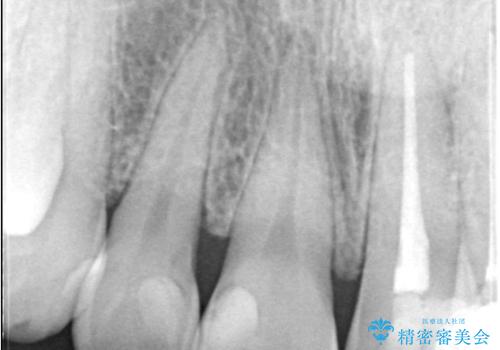

- 上顎の前歯4本が、過去の治療痕による変色や欠けで見た目が気になるとの主訴でご来院されました。患者様は、思い切り笑えるよう自然で美しい前歯を求めていらっしゃいました。そこで、最も天然歯に近い審美性を再現できるオールセラミッククラウンを用いた治療計画を立案しました。歯並びや色のバランスを整え、長期的に安定する美しい口元を獲得することを目指します。

治療はまず、審美性を最大限に高めるために、歯肉のラインや前歯の形を整えることから始めました。その後、4本の歯を丁寧に形成し、金属を一切使用しないオールセラミッククラウンを作製しました。